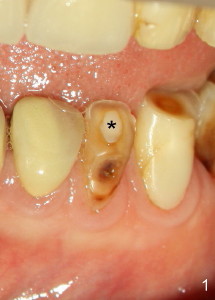

Sixty-two year old Chinese man presented to my office for new patient exam in June 2009. He has history of bruxism and wears night guard (Fig.1). The tooth #25 has incisal composite (*) with mild percussion. PAs show + PARL associated with #25 (Fig.2) and possible missing one canal (Fig.3; arrowheads point to possible 2nd root). RCT retreat was suggested. Extraction and implant were proposed as an alternative. In the next two 6-month appointments, he complained of mild pain in lower front tooth sometimes. RCT retreat was initiated on June 16, 2010. After removing composite, GP was removed with Chloroform and hand files. WL was determined by Root XZ at 15 mm. Debridement was done with hand files until #20 and rotary files until 30/.06 (Fig.4). The second canal was not found. It appears that some of GP was pushed outside of apical constriction (Fig.5 after Cavit). Twelve days later the patient returned to finish RCT retreat. It appears that symptoms improved after initiation of RCT retreat, although percussion is still mild. After removing Cavit and redebridement with #30 hand file, #10 precurved K file was inserted several times at different directions, hopefully getting into 2nd canal, which was not found. RCT filling was finished using AH Plus paste, master cone, lateral condensation with 1 medium fine accessory GP and vertical condensation (Fig.6). Composite build up was done immediately. Six months later, the patient insisted that pain is reduced substantially, but there is still mild percussion. PA shows persistent PARL (Fig.7 with outline with 2nd root (arrowheads)). Twelve months after RCT retreat, the patient is symptom-free, but objectively is not (including mild percussion and slightly enlarging PARL (Fig.8)). The 2nd canal is apparently lightly filled (red arrowhead).